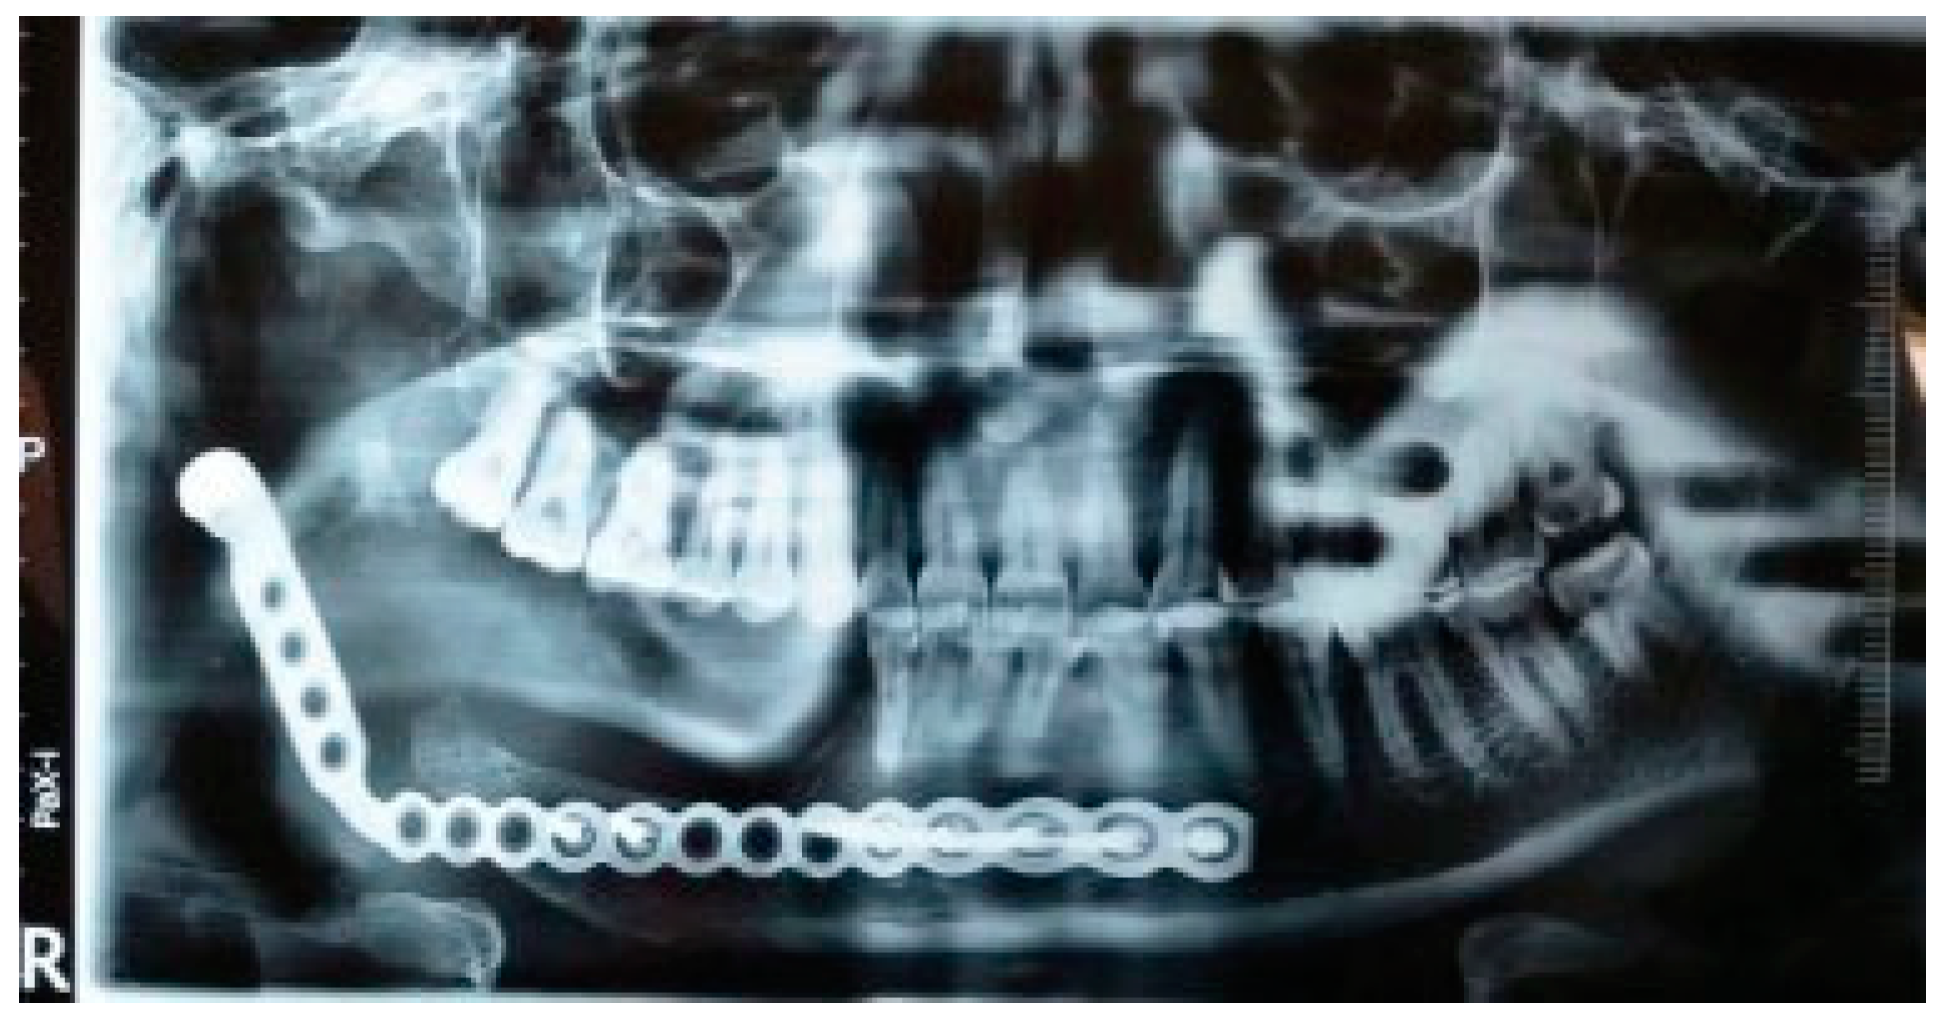

Postoperative recovery was fast and uneventful. As the swelling subsided gradually during the postoperative phase, excellent symmetry of the face was observed. Although the postoperative orthopantomogram (OPG) revealed that the condylar head of the plate was placed away from the glenoid fossa (Figure 9), the occlusion was intact with minor deviation of the jaw toward the resected side during mouth opening at the 6-month follow-up (Figure 10). Postoperative follow-up at 6 months shows appreciable facial harmony and maintenance of perioral musculature (Figure 11).

Figure 9. One-year postoperative orthopantomogram.